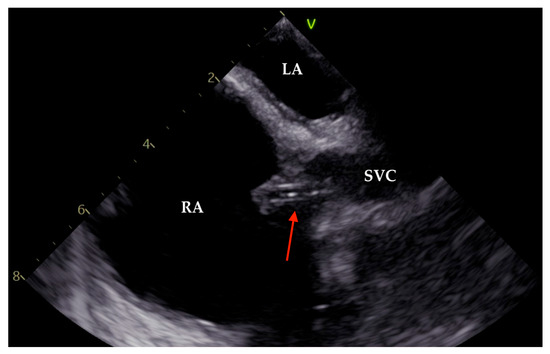

2. Case Presentation